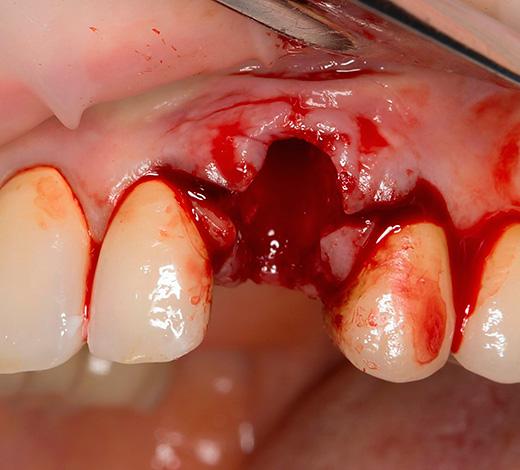

O fato de a gengiva durante o implante “não cirúrgico” sofrer lesões mínimas não exclui a necessidade de perfurar o osso da mandíbula usando um conjunto consistente de fresas. Afinal, a perna do implante é uma espécie de parafuso de titânio que você precisa literalmente parafusar no orifício.

Consequentemente, após realizar uma incisão circular com um mucótomo e remover o círculo gengival excisado, segue-se um estágio completamente padrão de preparação do orifício para a colocação do implante - expansão e aprofundamento dos cortadores.

Em primeiro lugar, qualquer intervenção cirúrgica associada a danos artificiais nos tecidos é considerada uma operação, mesmo que realizada da maneira mais suave e sem sutura. Portanto, é difícil chamar uma operação para cortar uma goma e a perfuração subsequente do osso maxilar.

Portanto, o implante dentário sem cortes na gengiva, a rigor, não existe: cortar a gengiva com alguma coisa e de alguma forma ainda precisa. Outra coisa é que existem ferramentas especiais que podem fazer cortes circulares precisos, cujo diâmetro é mínimo.